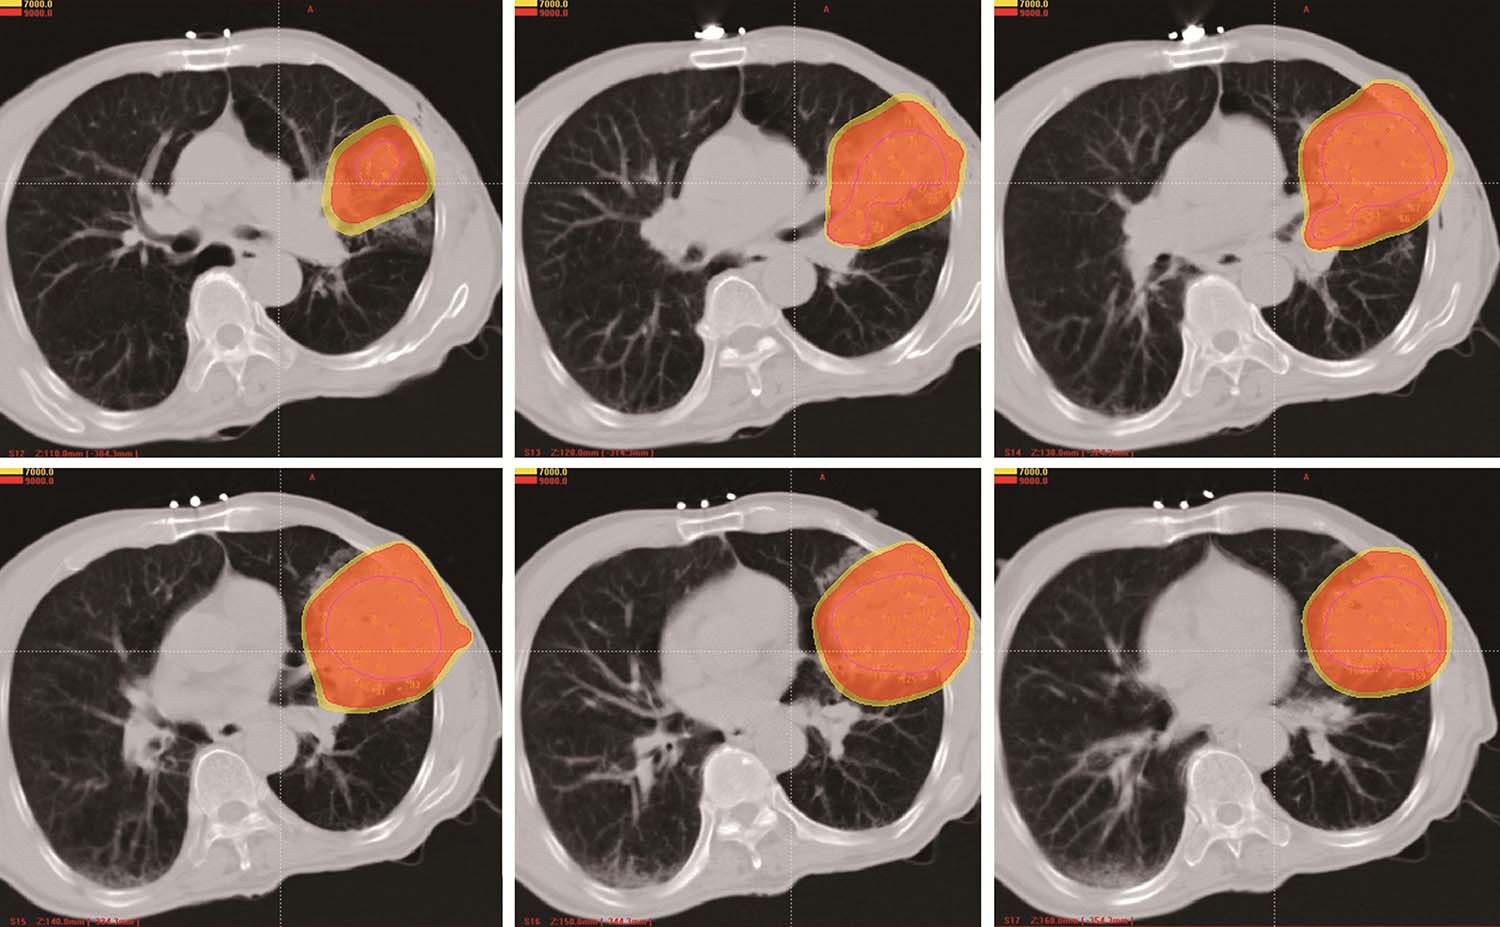

患者取与术前CT扫描相同体位,真空负压垫固定体位,防止穿刺过程中因体位变动给穿刺带来的不利影响。将导航支架与CT碳纤维床板相连接,以0.5cm层厚扫描,选取病灶中心层面,将一个预定进针点在皮肤表面做出大十字标记,消毒、铺巾、局麻,安装模板,用激光灯校准模板,使激光灯的 x 轴和 y 轴投影与模板表面的标记线相重合,利用数字化角度仪或者水平仪调整模板的角度和方向,使模板在 y 轴方向的角度为零,调整 x 轴方向的角度,与术前计划保持一致。选择病灶中心层面,参考术前计划,将数根穿刺针抵达皮肤表面,扫描观察针尾走行方向,再次校准模板,然后测量进针的深度,完成该层面的进针,如果是肺等移动度较大的脏器,可以先插入2~3根固定针,将病灶与模板迅速“绑定”(图4-3-1),然后再依次完成其他层面的进针,如果遇到坚韧骨骼遮挡,使用捻针或骨钻打孔技术破骨插植,待完成所有层面的进针以后再植入粒子。

图4-3-1 进针过程

例1 患者男性,72岁,左肺鳞癌侵犯胸壁并同侧肺门淋巴结转移,T4N1M0。2018年1月16日行共面模板引导放射性粒子植入术(图4-3-2~图4-3-7)。

例2 女性,76岁,左肺周围型腺癌,T4N0M0,2017年10月12日行共面模板引导放射性粒子植入术(图4-3-8~图4-3-13)。

图4-3-8 术前针道设计

图4-3-9 术前针道分布三维重建图

图4-3-10 共面模板引导,一次性完成所有层面进针

图4-3-11 术后等剂量分布图

图4-3-12 术后粒子分布三维重建图

图4-3-13 术后7个月复查,病灶明显缩小,疗效部分缓解